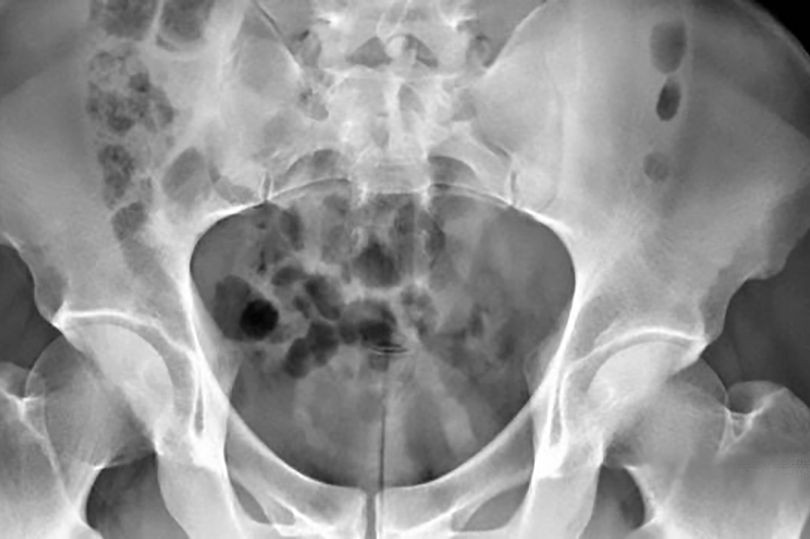

Chụp X quang cho thấy vật thể bằng nhựa dính vào niệu đạo của người đàn ông.

Bác sĩ Jiann Bang-bing, Trưởng Khoa Tiết niệu bệnh viện này cho biết: "Thanh nhựa dài 20cm và rộng 1cm. Các bác sĩ buộc phải sử dụng phương pháp nội soi vào bàng quang của người đàn ông để lấy đồ chơi tình dụng ra khỏi bàng quang. Hiện bệnh nhân được xuất viện và hồi phục hoàn toàn".